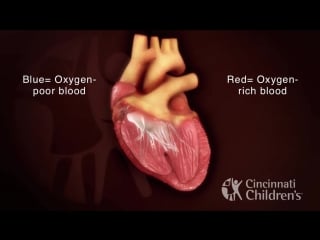

Atrial septal defect (asd)

This device helps patients with atrial septal defect (asd) also know as a hole in your heart

Atrioventricular septal defect av canal